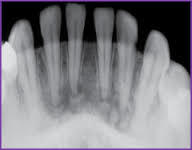

Cleidocranial Dysplasia

Characterized by clavicle and dental abnormatlities

Clavicles – varying degress of hypoplasia (unusual mobility of shoulders)

Appearance (DIAGNOSTIC): Short stature, big head. Pronounced frontal bossing, Occular hypertelorism, broad base of nose

Oral ->

HIGH arched palates.

increased prevalance of cleft palate

Prolonged retention of deciduous teeth

Delay or failure of eruption or permanent teeth

Abnormally shaped teeth

**Numerous unerrupted permanent teeth and supernumerary teeth **

No treatment

Oral complications of cleidocranial dysplasia

High arched palate

INCREASED prevalence of cleft palate

Delayed or failure of eruption of permanent teeth

Numerous unerupted permanent and supernumerary teeth